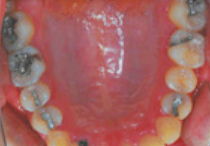

BEFORE

AFTER

충치 부위가 넓거나 힘이 강한 어금니 부위에는

충분한 강도를 가지고 있는 금으로 수복하게 됩니다

금의 특성상 색깔 때문에 눈에 띄는 부위에 사용하는 것을 꺼려 하시기도 하지만 뛰어난 물리적 성질 때문에 널리 사용되는 치료법입니다.